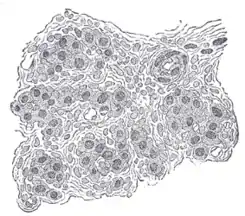

![]() Sección muy ampliada del glomus carotídeo. Se observan los numerosos vasos sanguíneos que lo irrigan. | ||